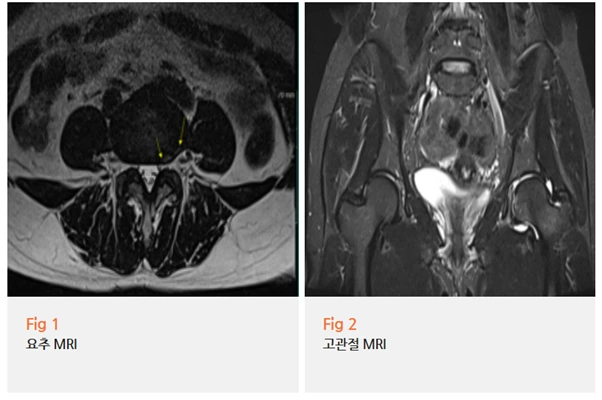

저는 이 환자분께 당일 요추와 고관절 MRI를 함께 촬영할 것을 권유드렸어요.

결과를 보니, 요추 4-5번의 추간판 탈출 소견이 함께 있었고

좌측 고관절 부위에서는 염증 소견이 확인되었어요.

진단은 고관절충돌증후군이었습니다.

저는 요추 MRI와 고관절 MRI를 동시에 촬영해보자고 말씀드렸습니다.

고관절 자체에는 이상 소견이 없었고,

요추 3-4번 사이에서 추간판이 탈출해 상방으로 이동한 소견이 확인됐어요.

이 탈출된 디스크가 신경근을 압박하면서

좌측 둔부와 고관절 바깥쪽 방향으로 통증이 퍼진 전형적인 방사통 패턴이었어요.